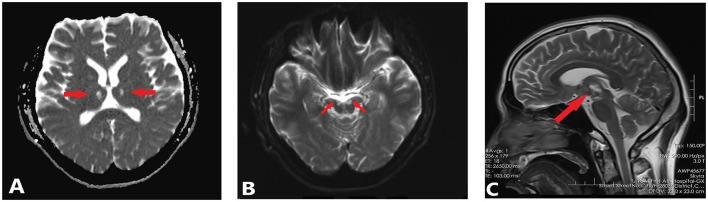

针刺治疗电创伤继发丘脑和中脑损伤:一例报告。

Acupuncture for the treatment of thalamencephalic and mesencephalic injury secondary to electrical trauma: A case report.

In a case of thalamencephalic and mesencephalic injury secondary to electrical trauma, a 29-year-old patient has been receiving manual acupuncture for 17 months in National Clinical Research Center for Chinese Medicine Acupuncture and Moxibustion. As a result of treatment, the patient's self-care ability and quality of life have greatly improved. In order to fully understand how acupuncture can benefit neurological sequelae resulting from electrical trauma, further research is needed. Additionally, there should be consideration given to the promotion of acupuncture therapy in the neurological sequelae of electric shock.

在一例因电击伤继发丘脑和中脑损伤的病例中,一名29岁患者在国家中医针灸临床研究中心接受了17个月的手动针灸治疗。经过治疗,患者的自我护理能力和生活质量有了很大提高。为了充分了解针灸如何有益于电击伤所致神经后遗症,还需要进一步研究。此外,应考虑在电击伤神经后遗症中推广针灸疗法。